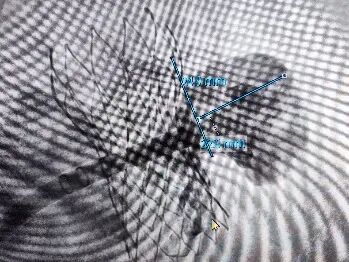

CTA锚定封堵开口平面分析

CTA模拟TEE观察左心耳

由于患者高龄,术前未行TEE检查,CTA检查后,提示患者左心耳内无血栓。多平面肝位重建分析患者左心耳开口24.6mm,模拟TEE检查左心耳开口21.5mm-24.7mm,左心耳口部封堵面分析平均开口直径24mm,肺静脉脊较长,左心耳深度较浅,拟选用WATCHMAN FLX™ 31mm封堵器封堵。